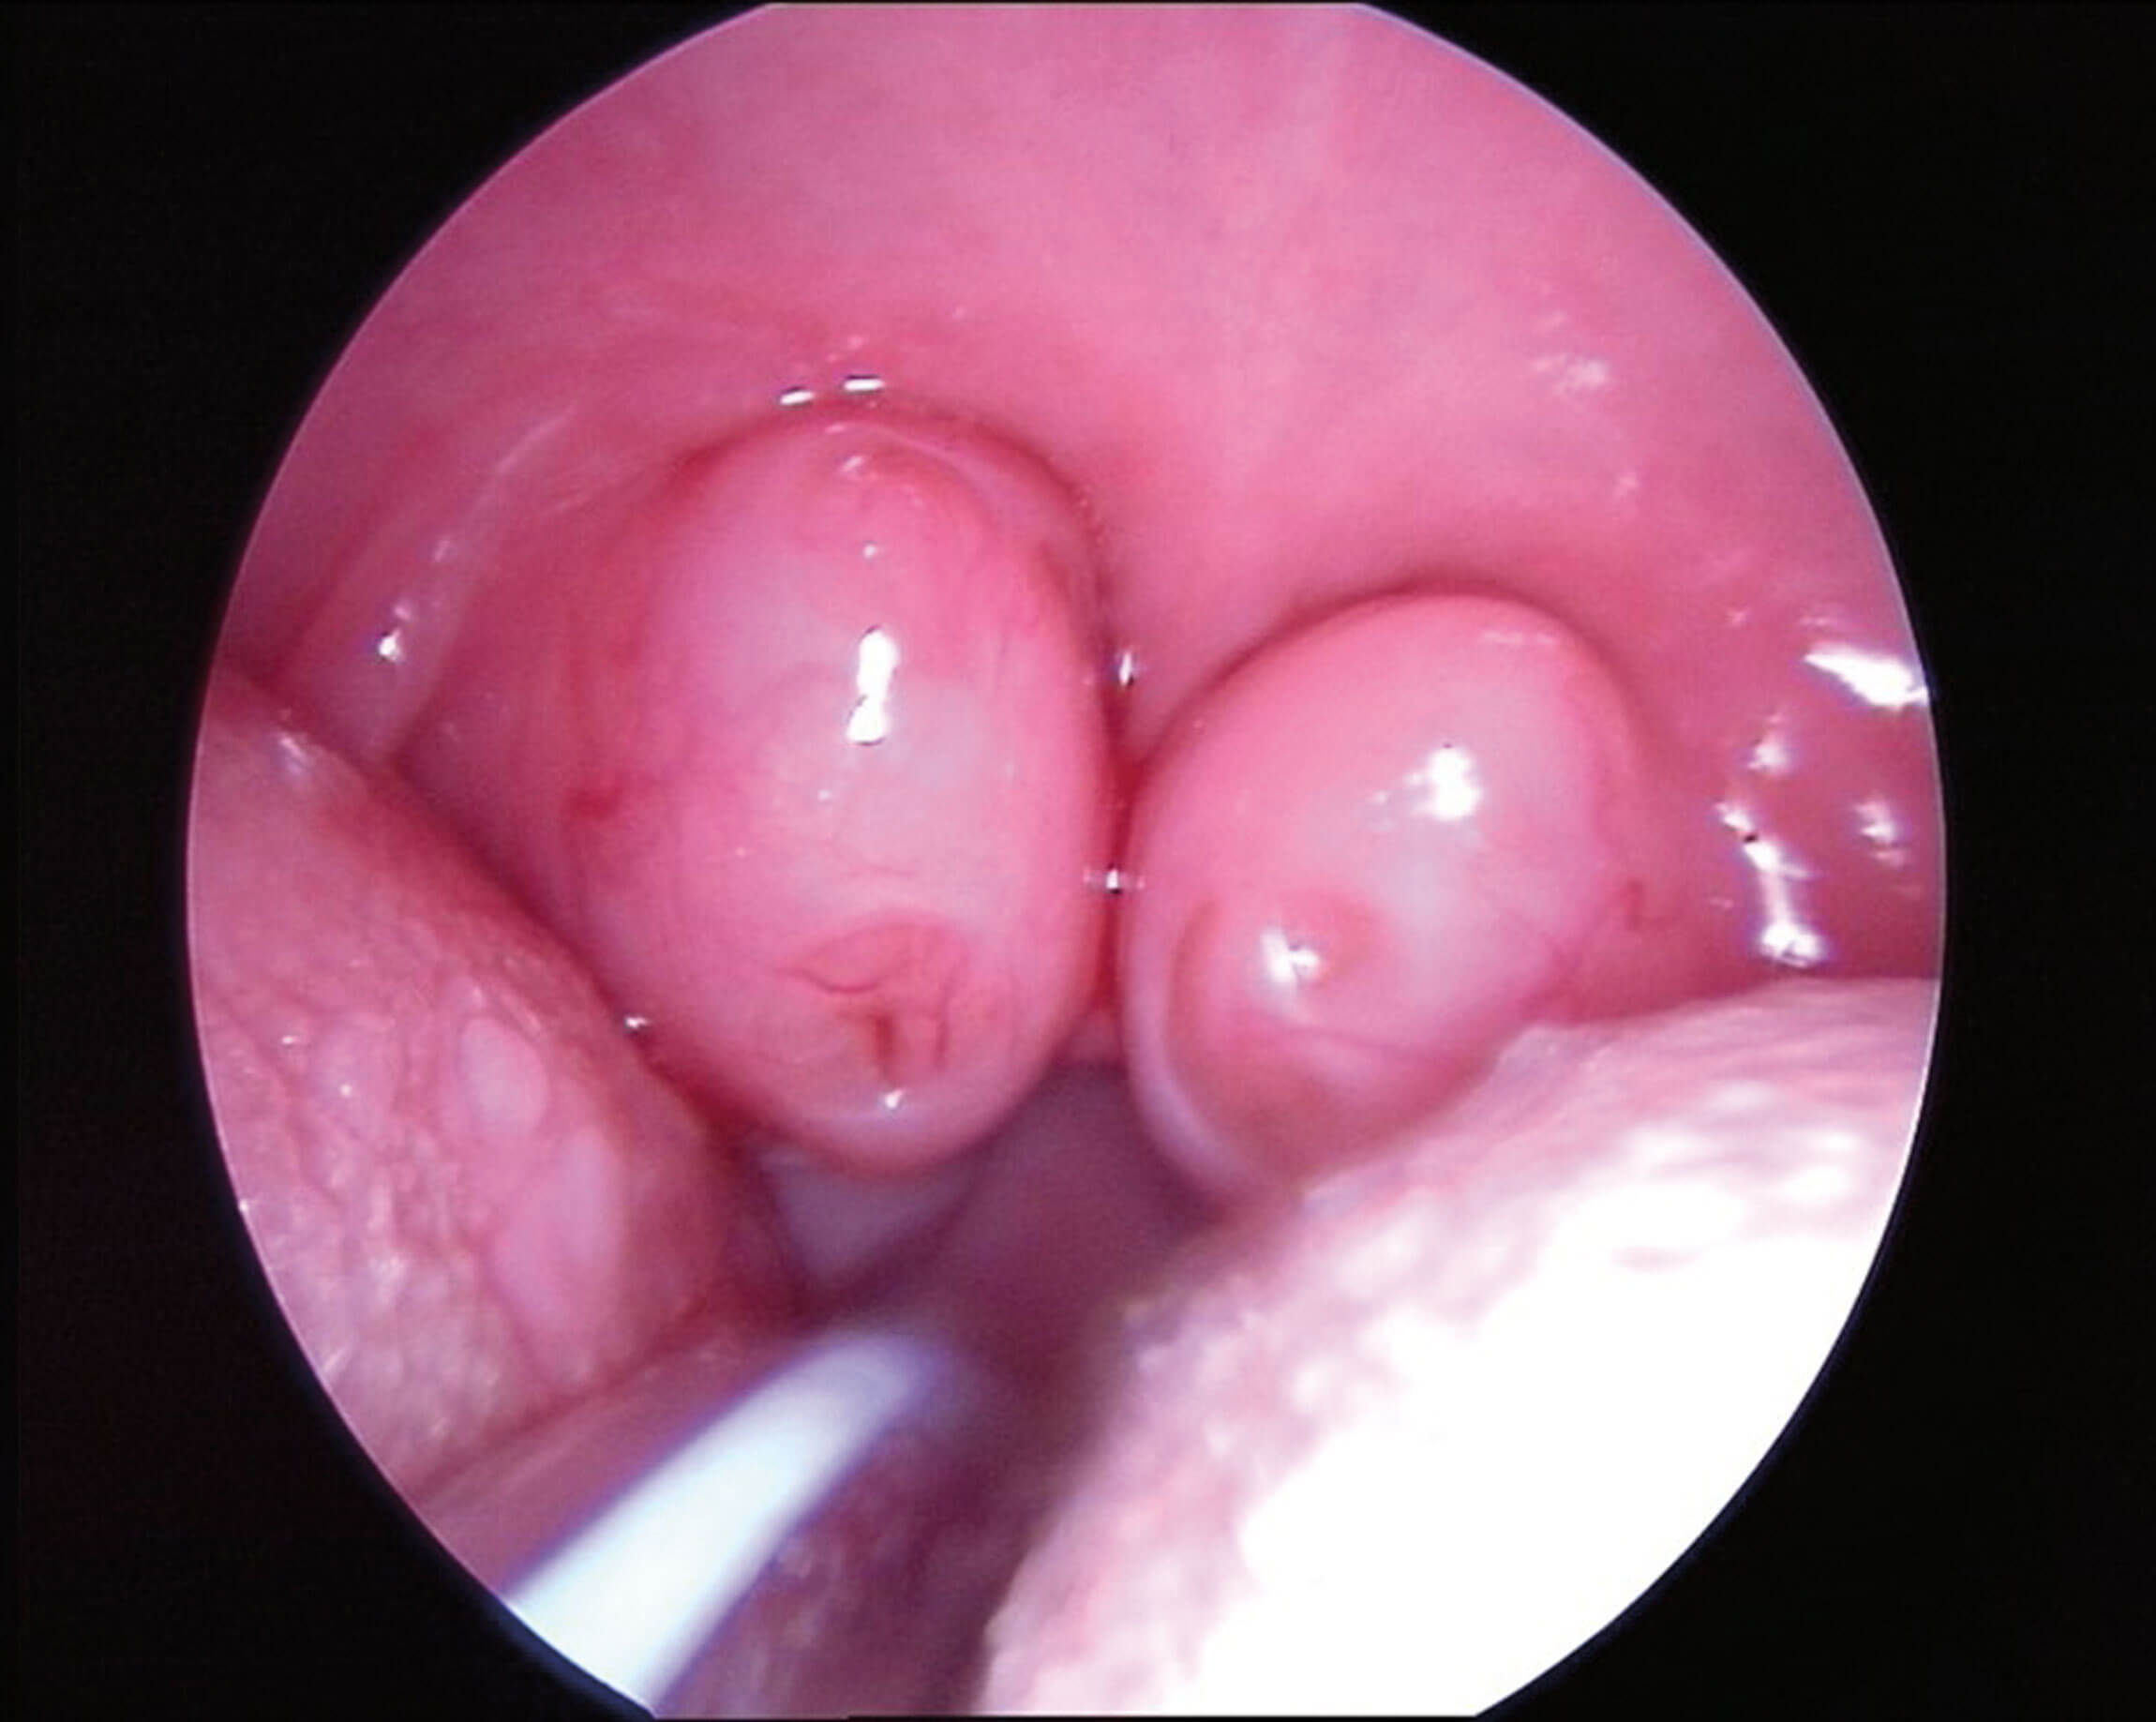

Trying to combine work and family time is one of the key issues of the younger generation. As time spent in the operating theatre decreases in comparison to previous generations, alternative ways to train are emerging through simulation or videos. Young ESPO is trying to accompany this with the educational video contest. Indeed, numerous scientific articles have shown that freely accessible online surgical videos are becoming more and more important in the training process of younger surgeons. Editing surgical videos to be short and to the point (usually five minutes or less), adding overlays to show anatomy, clearly identifying surgical steps and adding narration are all key features which improve the educational quality of a video.